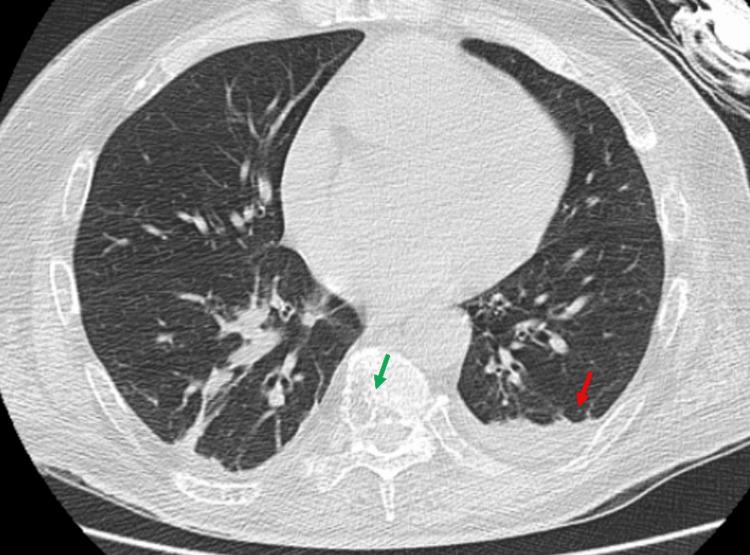

Multiple myeloma (MM) is a neoplastic proliferation of plasma cells in bone marrow. Pharmacotherapy for the management of patients with MM includes drug classes like proteasome inhibitors, monoclonal antibodies, immunomodulators, alkylating agents, steroids, etc. We present a case of new-onset heart failure with reduced ejection fraction (HFrEF) in a patient with previously normal ejection fraction after treatment with a cyclophosphamide, bortezomib, and dexamethasone (CyBorD) chemotherapeutic regimen. An echocardiogram done after the completion of nine cycles of chemotherapy in a period of about 4.5 months showed severely decreased left ventricular systolic function with an ejection fraction of only 15-20% and grade I diastolic dysfunction. Cardiac catheterization showed no angiographic evidence of vessel occlusion or epicardial disease. HFrEF was managed with the initiation of guideline-directed medical therapy with cardiology clinic follow-up, and the patient was discharged with a plan to start a lenalidomide-based chemotherapeutic regimen with oncology clinic follow-up. It is, therefore, imperative to perform a thorough cardiovascular assessment before initiation of chemotherapy, complemented by periodic and recurrent assessments of cardiovascular function during and after completion of the treatment course, for early detection and prevention of potentially severe cardiovascular toxicities in patients with MM.

多发性骨髓瘤(MM)是骨髓中浆细胞的肿瘤性增殖。用于治疗MM患者的药物疗法包括蛋白酶体抑制剂、单克隆抗体、免疫调节剂、烷化剂、类固醇等药物类别。我们报告一例患者,在用环磷酰胺、硼替佐米和地塞米松(CyBorD)化疗方案治疗后,出现了射血分数降低的新发心力衰竭(HFrEF),而该患者之前的射血分数正常。在约4.5个月的时间内完成九个周期化疗后进行的超声心动图显示,左心室收缩功能严重下降,射血分数仅为15% - 20%,且存在I级舒张功能障碍。心导管检查未发现血管闭塞或心外膜疾病的血管造影证据。通过启动基于指南的药物治疗并进行心脏病学门诊随访来管理HFrEF,患者出院时计划开始基于来那度胺的化疗方案并进行肿瘤学门诊随访。因此,在开始化疗前进行全面的心血管评估,并在治疗过程中和治疗完成后定期反复评估心血管功能,对于早期发现和预防MM患者潜在的严重心血管毒性至关重要。